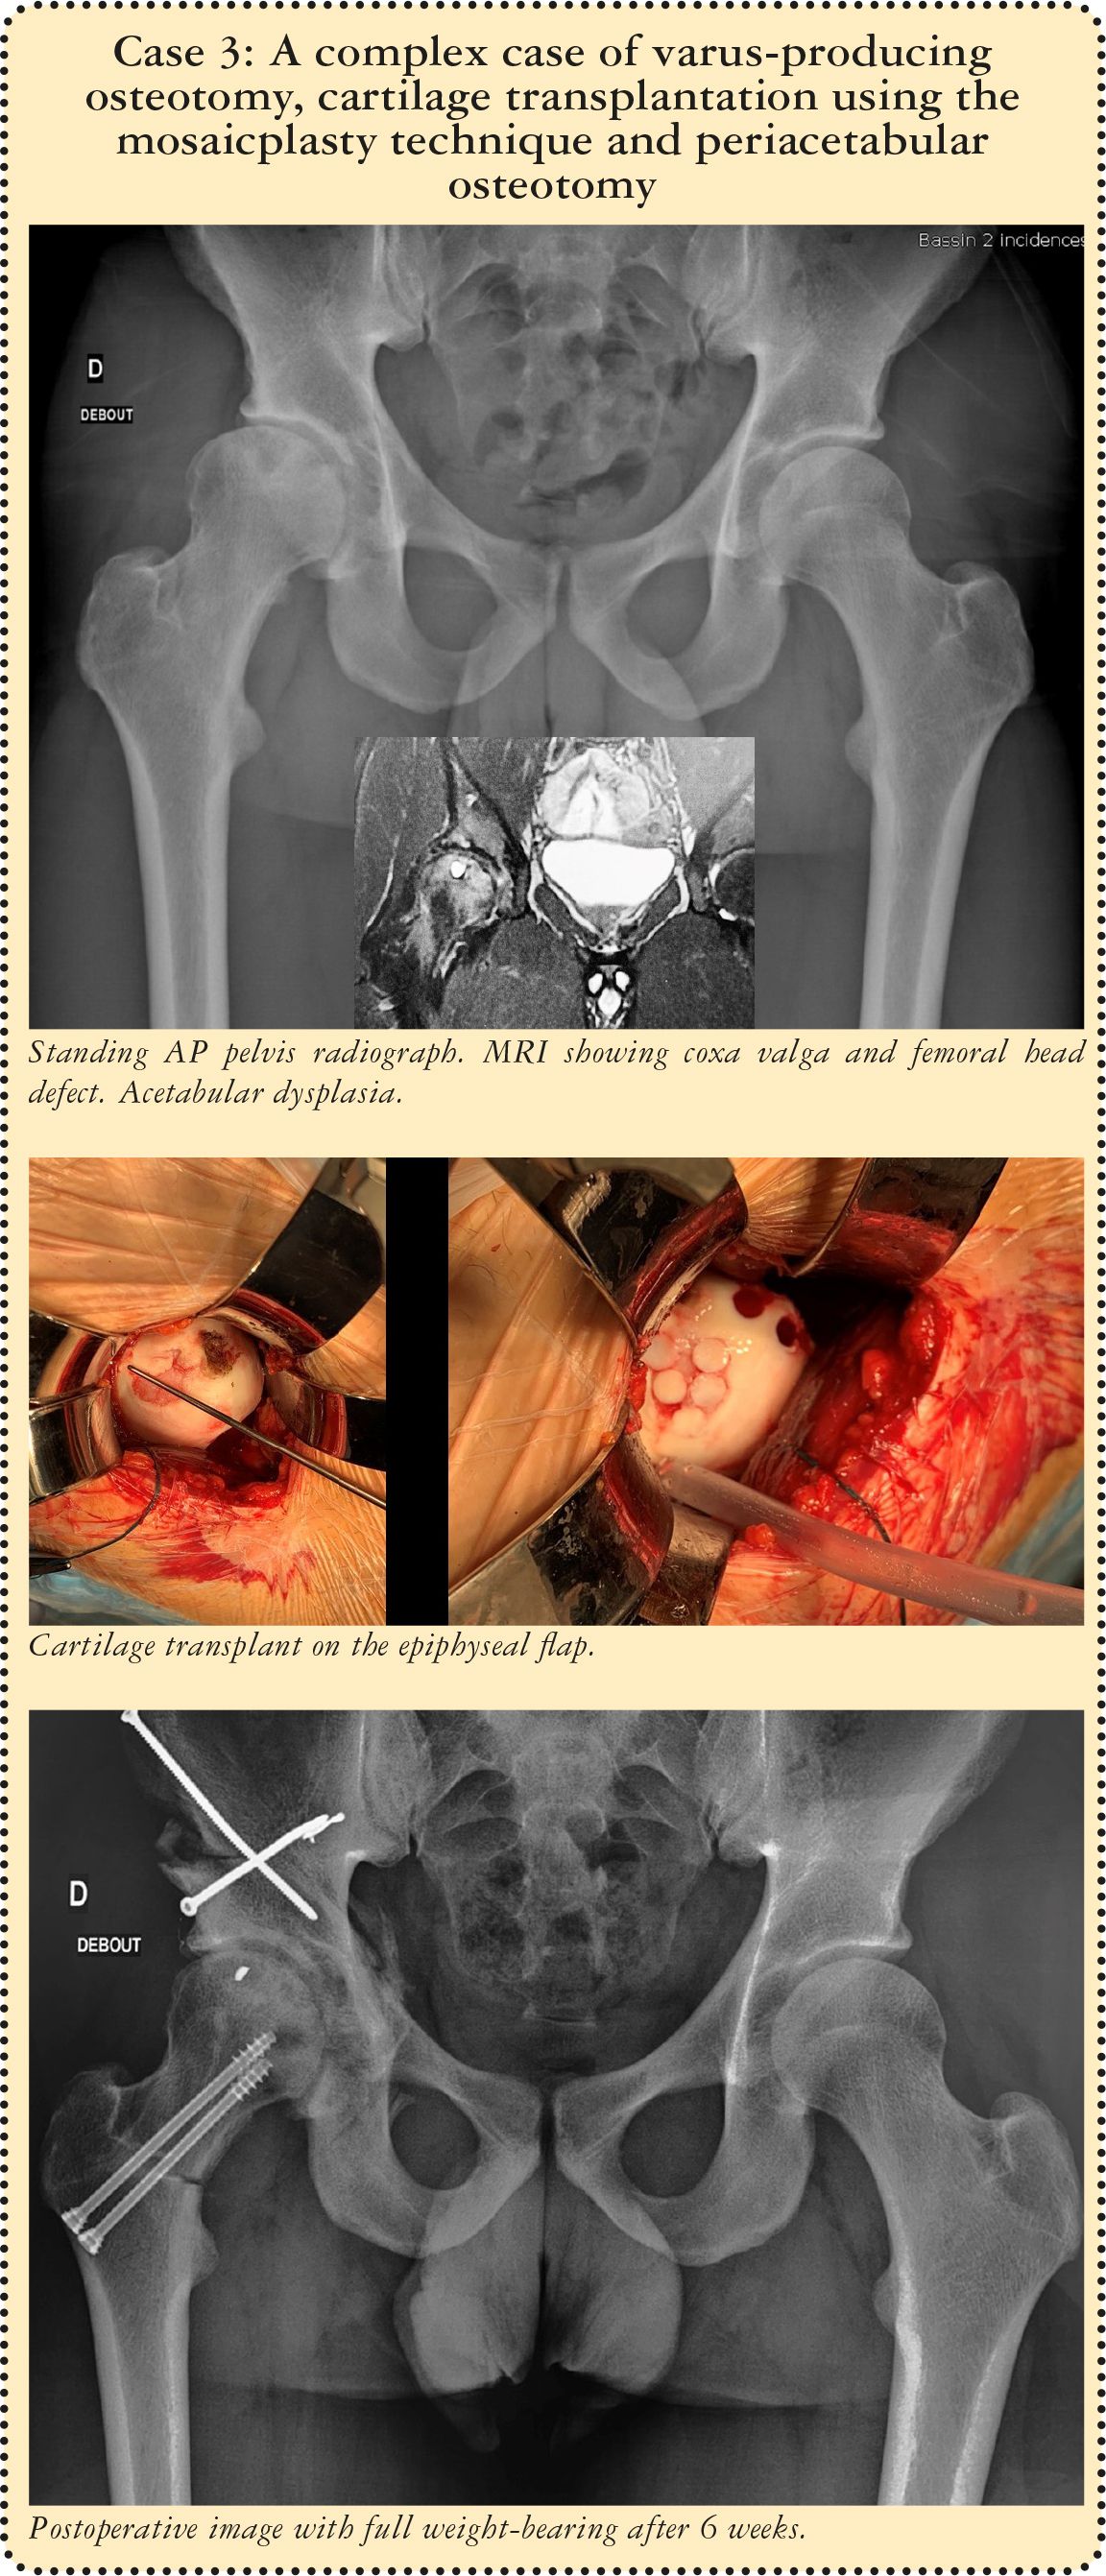

Two patients underwent a simultaneous periacetabular osteotomy. In one of these two cases, involving a young 27-year old patient, the periacetabular and varus osteotomy were accompanied by a cartilage transplantation using the mosaicplasty technique with anterior femoral dislocation. All three procedures were of course performed through the same portal.

Hip dysplasia is often a multi-factorial condition. In some cases, as in our series or that of Buly,[19] the femoral osteotomy must be accompanied by an additional surgical procedure such as periacetabular osteotomy, hip arthroscopy or mosaicplasty. In both of the techniques described above, this additional procedure will require additional incisions or portals.

Our technique however has the advantage of involving one single small incision through which any additional procedure can also be performed with ease. With a periacetabular osteotomy,[20] the scar extends to the iliac crest with or without avulsion of the anterior superior iliac spine.